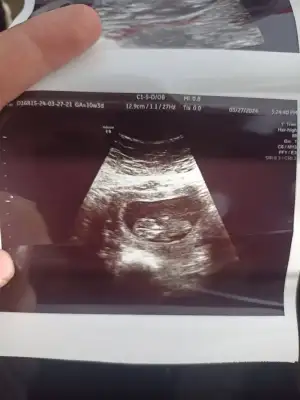

Banada yorum yaparmisiniz acaba ilk foto 13+6 Ken olan ulturoson resmi ikincide 6+7 haftalık ulturoson resmi şuan ,16 haftaligiz fktotumuz hala cinsiyet söylemedi